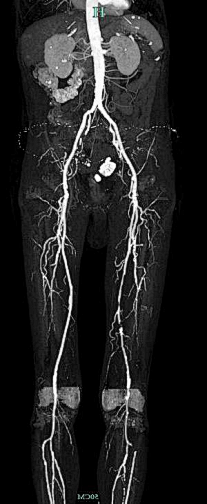

术前CTA:腹主动脉及双下肢动脉粥样硬化改变,左股浅动脉中下段重度狭窄接近闭塞,左股浅动脉下段、腘动脉、膝下分支多处钙化病变。

右侧股动脉翻山入路,经鞘管造影显示下肢动脉多发硬化改变。

左侧股浅动脉中下段局部重度钙化狭窄闭塞,左股浅动脉下段,腘动脉局部中度钙化狭窄。

股浅动脉

腘动脉